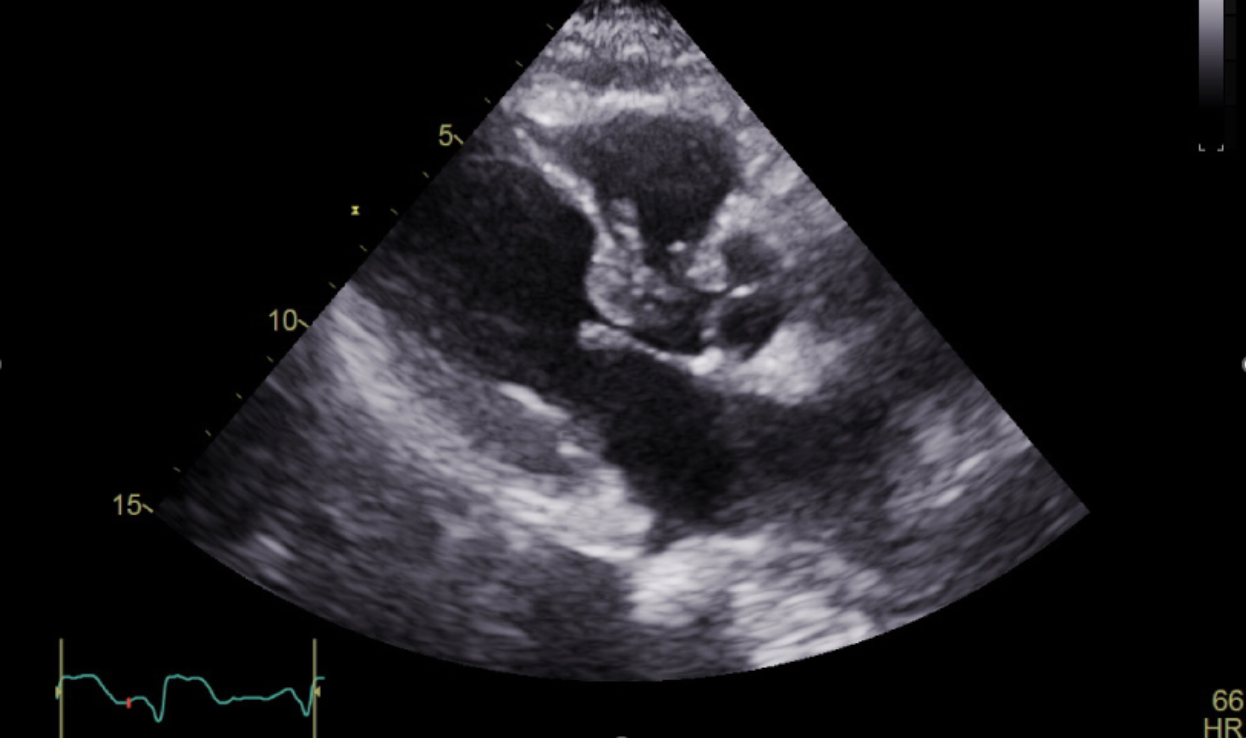

ECG showed tachycardia with new anterolateral Q waves and ST elevation in V2–V5, prompting STEMI activation. Bedside echo showed apical and inferoseptal akinesis. Coronary angiography was deferred due to delayed presentation and down-trending high-sensitivity troponin (618 ng/L). She was admitted to the CCU, where shock improved with norepinephrine, milrinone, and IV diuresis.

Her course was complicated by new-onset atrial fibrillation with RVR. Despite IV amiodarone, RVR persisted, along with worsening respiratory status and increasing vasopressors needs. Limited echocardiography revealed basal hypercontractility and dynamic LV outflow tract obstruction (LVOTO). Esmolol was considered to reduce the gradient. Simultaneously, pulmonary artery catheter readings suggested new left-to-right shunting. A new loud holosystolic murmur was heard, and repeat echocardiogram confirmed a large ventricular septal rupture (VSR).